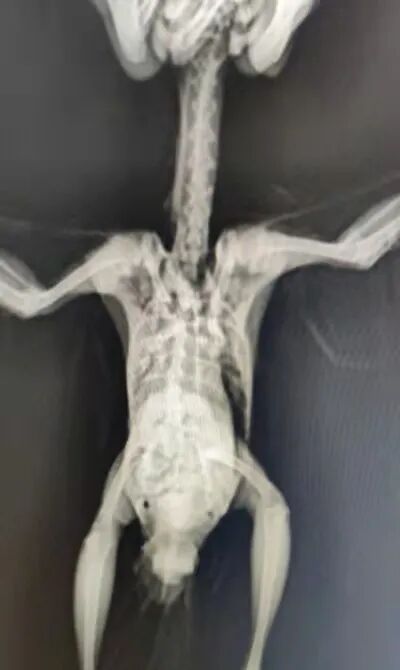

▶一只白鹭上青天

9月25日,让候鸟飞志愿者亭子在四川省成都市江安河边看到一只小白鹭,目测没有受伤。人靠近以后,小白鹭会张开翅膀,但不会飞走。亭子担心牠可能有伤或者中毒,在鸟医部军老师的建议下将小白鹭带走照料。

带回家后,亭子给牠做了检查。小白鹭龙骨明显突出,嗉囊没有东西,应该是挨饿了。军老师建议先去买一些活鱼喂食,不要太大,但一定要鲜活,这样可以激发小鸟食欲。

小白鹭不肯吃东西,军老师建议进行填喂,至少要喂食一条。同时将小鸟安排在大小合适的盒子或者箱子里面,在箱底放养一些泥鳅,留下适度灯光,夜深人静时小鸟或许会吃食。

通过亭子发来的影像资料,军老师判断:小白鹭双翅未见有伤,双脚缺乏力度,虽有喝水行为,但对小鱼没有食欲,整体诊断小鸟身体处于不适状态。亭子决定先让牠休息一晚,次日再观察情况。

26日早上,为了判断小鸟的情况,亭子观察了牠的排泄情况。小鸟大便正常,精神有所恢复,扑腾扑腾地想从箱子里面逃出去。军老师提醒,小白鹭吃食不太利落,没有力气,可以去花鸟市场买些食蚊鱼,个头小巧便于饮食。小鸟的状态正在逐渐好转,更应该锻炼牠自己啄食的能力。

26日傍晚,亭子欣喜地发现,小白鹭有在偷偷吃泥鳅了,说明情况已经好转,悬着的心终于放下。军老师判断小鸟之前可能有过中毒经历,幸运地是并不严重,靠着自身体能扛了过来,得到救助后很快就能恢复了。

27日的时候,小白鹭大口吃鱼,翅膀狂野有力,但就是飞不起来。军老师建议再让牠修养一晚,睡前多多喂食,次日再去找到小鸟的地方放飞。

又经过一段时间的休养,29日这天,亭子带着小白鹭回到了捡拾地。小白鹭扇动翅膀,一下就冲到了对岸,水平飞行,一气呵成。希望未来牠能在水天一线间无忧无虑,自由翱翔。